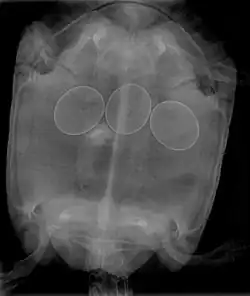

Bei Schildkröten kann eine operative Entfernung der Eier nötig werden.